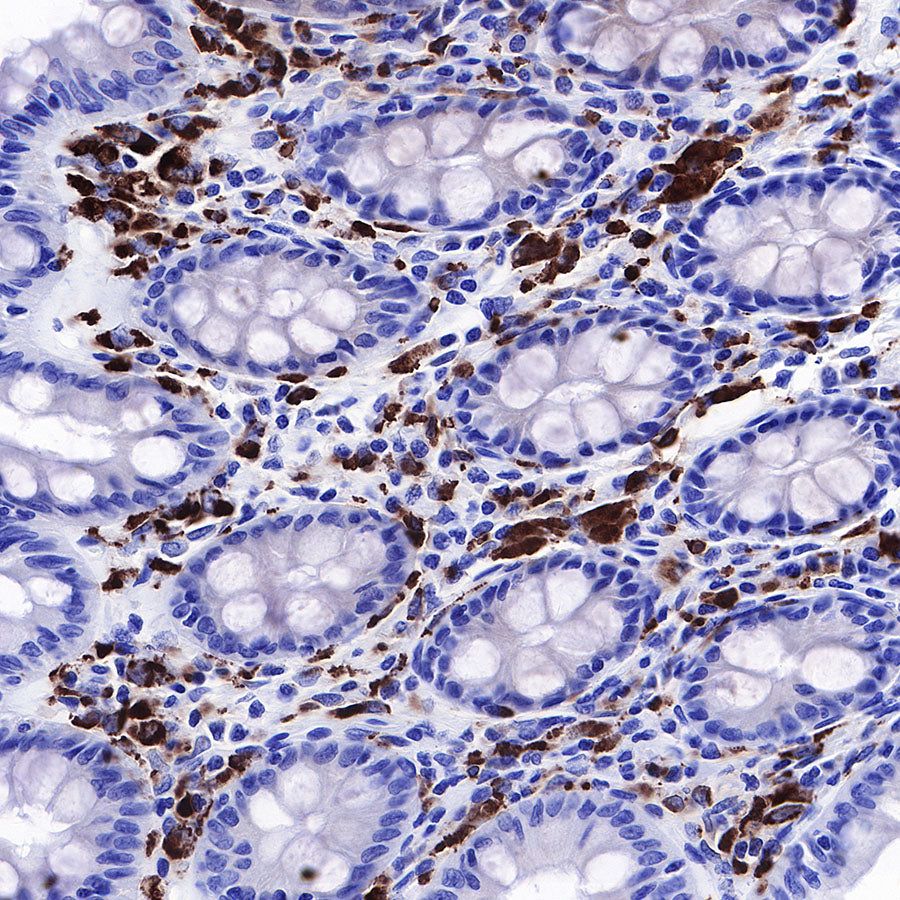

IHC shows positive staining in paraffin-embedded human colon. Anti-CD68 antibody was used at 1/1000 dilution, followed by a HRP Polymer for Mouse & Rabbit IgG (ready to use). Counterstained with hematoxylin. Heat mediated antigen retrieval with Tris/EDTA buffer pH9.0 was performed before commencing with IHC staining protocol.